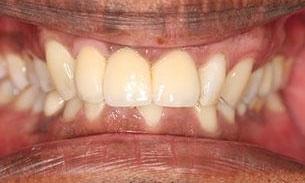

The patient wanted to be able to smile when she retires and travels around. An infected upper incisor was removed before a carefully designed ceramic bridge and a crown were placed. She was so thrilled with the result! Now she can show her teeth when she smiles in her photos.